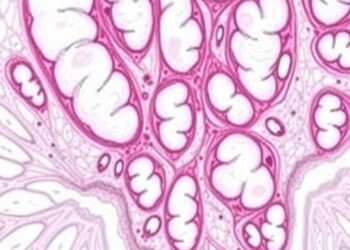

TP53 Mutations Linked to Poor Prognosis in DLBCL

In a pivotal research study published in the Journal of Cancer Research and Clinical Oncology, scientists have unearthed important genetic ...

In a groundbreaking study led by researchers at The University of Osaka in collaboration with the Massachusetts Institute of Technology, ...